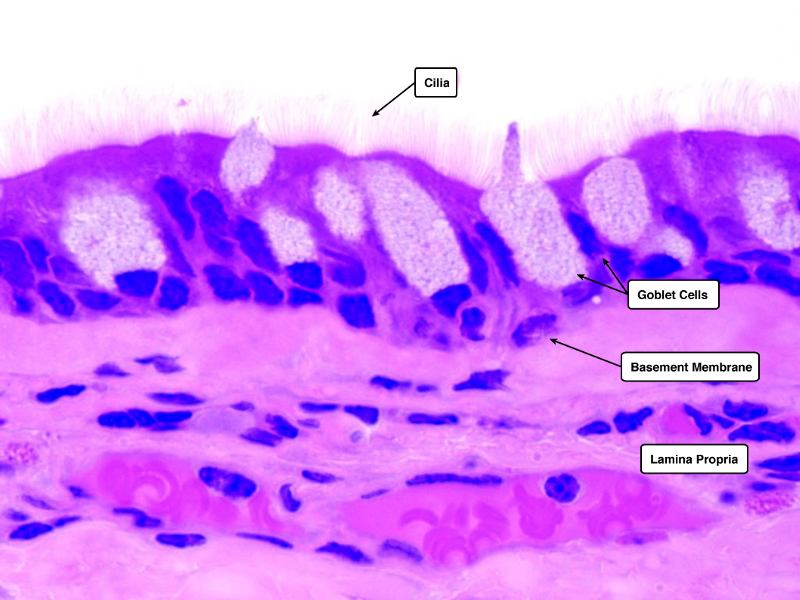

Identify and describe the epithelium on the following slide:

Pseudostratified columnar epithelium

What cells are present?

- Goblet cells

- Basal cells

- Ciliated columnar cells

- Unciliated columnar cells